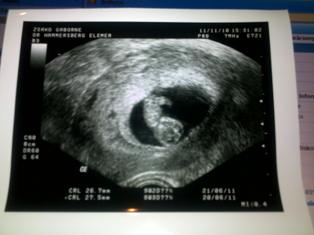

Ha minden igaz, akkor hétfőn megnzének, aztán szerdán lesz a lezsívás, ha a hétfői ultrahang jót mutat. Gondolom, hogy szombaton kapom majd vissza őket - főleg, hogy ilyen tortúraként indul az egész.